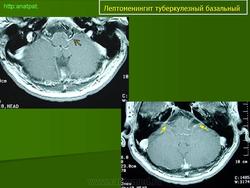

Туберкулёз.

Приложения:

1.t.slayd109.jpg2.t.slayd110.jpg3.t.slayd111.jpg